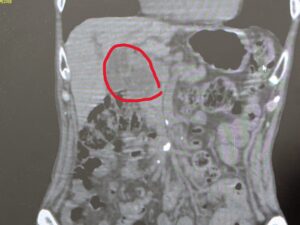

普段高血圧で総合病院に通院している90代の元気な方です。

あしのむくみが気になり、ご家族と受診されました。

CTで膵臓に腫瘍を認めます